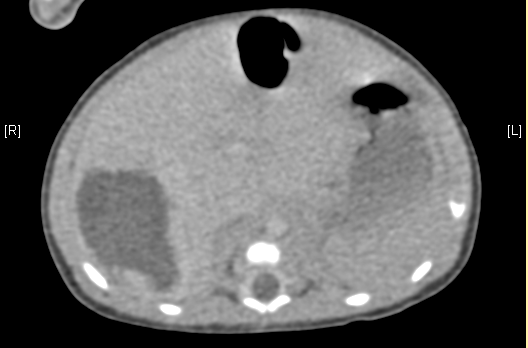

上腹部增强CT:肝脏右后叶血管源性肿瘤可能性大。上腹部增强CT:肝脏右后叶血管瘤可能性大。

术前CT检查:

动脉期

静脉期

平衡期